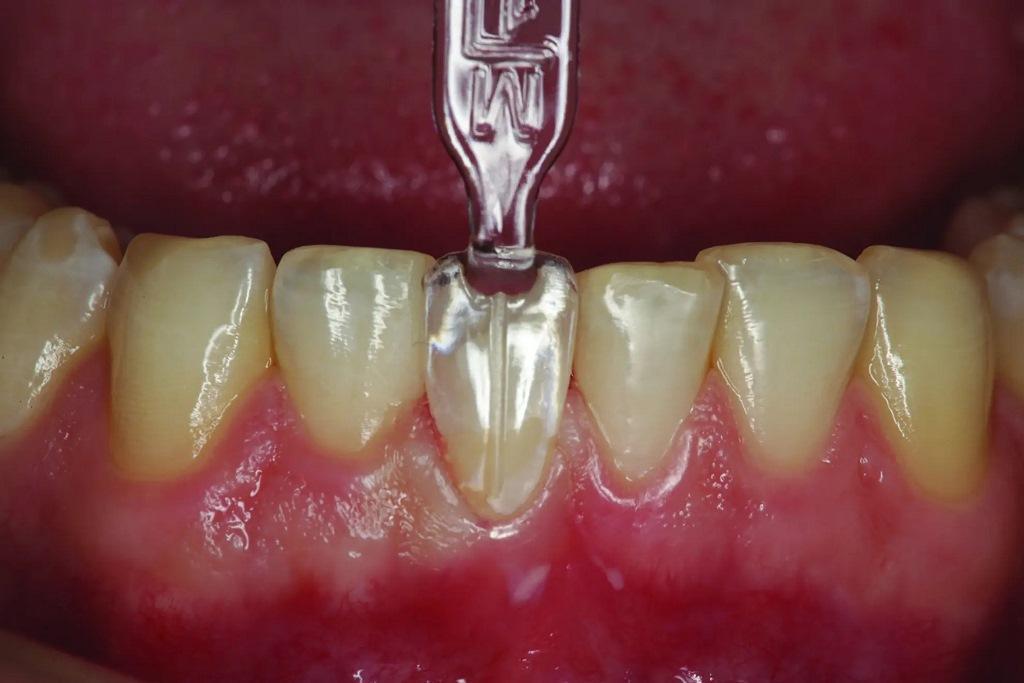

Оттенок был выбран предоперационно и сфотографирован для керамиста с целью подбора цвета с помощью цифровой камеры с функцией, позволяющей изолировать оттенок зуба от остальной части полости рта (EyeSpecial C-II, Shofu; фото 4). Затем лицевая поверхность зуба 41 была подготовлена для перемещения лицевой поверхности и режущего края в язычном направлении (фото 5). После подготовки скошенная лицевая поверхность зуба 41 имела острый пришеечный край около 2 мм наддеснево. Этот длинный скос позволил добиться более эстетичного сочетания композита и структуры зуба, оставив при этом профиль прорезывания естественного зуба нетронутым.

Фото 5: Зуб 41 ортодонтически препарирован с лицевой стороны, чтобы создать пространство для восстановления этой поверхности, которое могло бы скорректировать лицевое положение зуба при окклюзии.